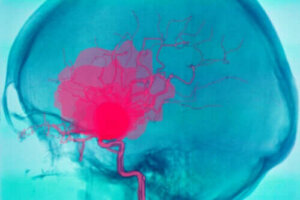

Een intracerebrale bloeding is een ernstige situatie die het leven van iemand in gevaar kan brengen. Het bestaat uit een bloeding in de hersenen. Hierdoor krijgen andere lichaamsdelen geen zuurstof.

Een intracerebrale bloeding, zoals we in de inleiding al noemden, is een bloeding die in de hersenen optreedt. Het veroorzaakt meestal plotseling optredende neurologische defecten en soms zelfs coma.

Dit komt door het gebrek aan bloedtoevoer naar andere delen van de hersenen (Spaanse link), aangezien het bloed zijn reis door de bloedvaten niet voortzet. Het is belangrijk om een onderscheid tussen een intracerebrale en een intracraniële bloeding te maken.